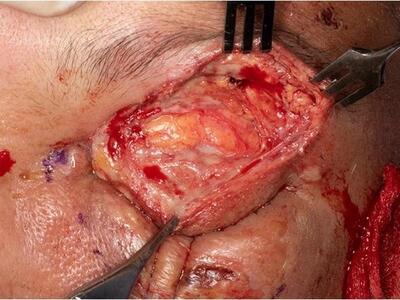

This was a 62-year-old man with type 2 diabetes who was assaulted with a wooden plank and rusty nail on his frontal scalp area sustaining a laceration 3 days prior. The laceration was sutured and a head injury was ruled out with a CT scan.